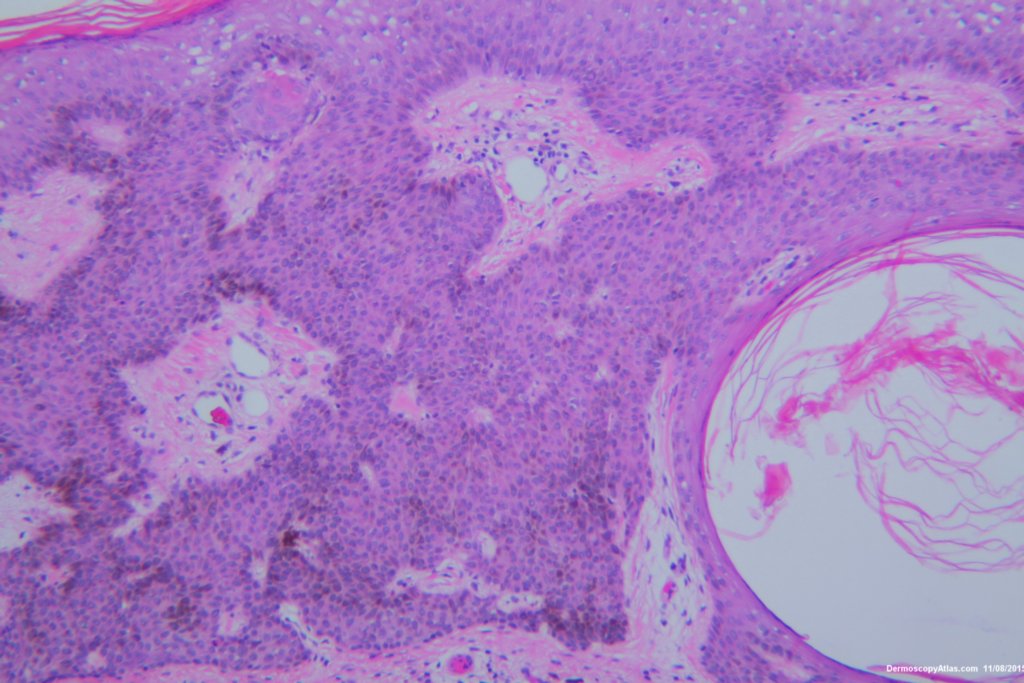

Image Number #3374 (Seborrhoeic keratosis irritated)

Diagnosis: Seborrhoeic keratosis irritated

Description: Pigmented lesion back

This lesion looked darker than the many other seborrhoeic keratoses on this elderly man's back. It was thought there might be a lentiginous proliferation of atypical melanocytes in the lesion . Also the multiple colours and the white lines were unusual for a seborrhoeic keratosis. However pathology of a large shave biopsy excision showed only a pigmented thick seborrhoeic keratosis with increased pigment in normal basal keratinocytes. The blue colour was because of the depth of the lesion ie thick. No idea why the white lines!